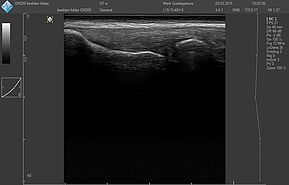

Области исследований:

- Брюшная полость

- Акушерство и гинекология

- Урология

- Щитовидная железа

- Молочная железа

- Кардиология

- Костно-мышечная система

- Педиатрия

- Нейросонография

- Исследование сосудов

- Транскраниальные исследования

Датчики имеют большую чувствительность и высокое разрешение, благодаря чему обеспечивают максимальное проникновение и улучшают соотношение сигнал /шум. В результате формируется максимально четкая детализированная картинка УЗИ изображения.